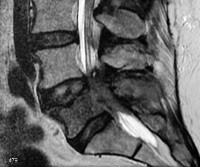

• МРТ пояснично. Крестцового отдела. Исследование осуществляется для визуализации опухоли, уточнения её размеров, распространённости, характера роста, наличия капсулы. При невозможности проведения МРТ выполняется КТ позвоночника с контрастированием.